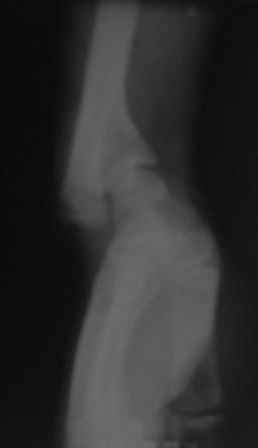

С учетом возраста больного предлагаемая Вами тактика представляется оптимальной. Боковая ренгенограмма низкого качества, но кажется дистальный фрагментдостаточно короткий - надо постараться выполнить остеотомию точно на высоте деформации иначе трудно будет устранить угол.

Под рукой оказалась минирентген локтевого сустава, где можно увидеть cubita valga(последствие надмышелкового перелома).

Уважаемый коллега, так, может быть, пытаясь восстановить длину, не менее важно восстановить и ось конечности, - Вы это сможете объяснить пациенту, а сами, выполняя остеотомию дистального метаэпифиза плечевой кости с целью коррекции оси, получите еще 1,5 - 2,0 см дополнительного удлинения.

Я думаю, что ось локтевого сустава исправлять надо.